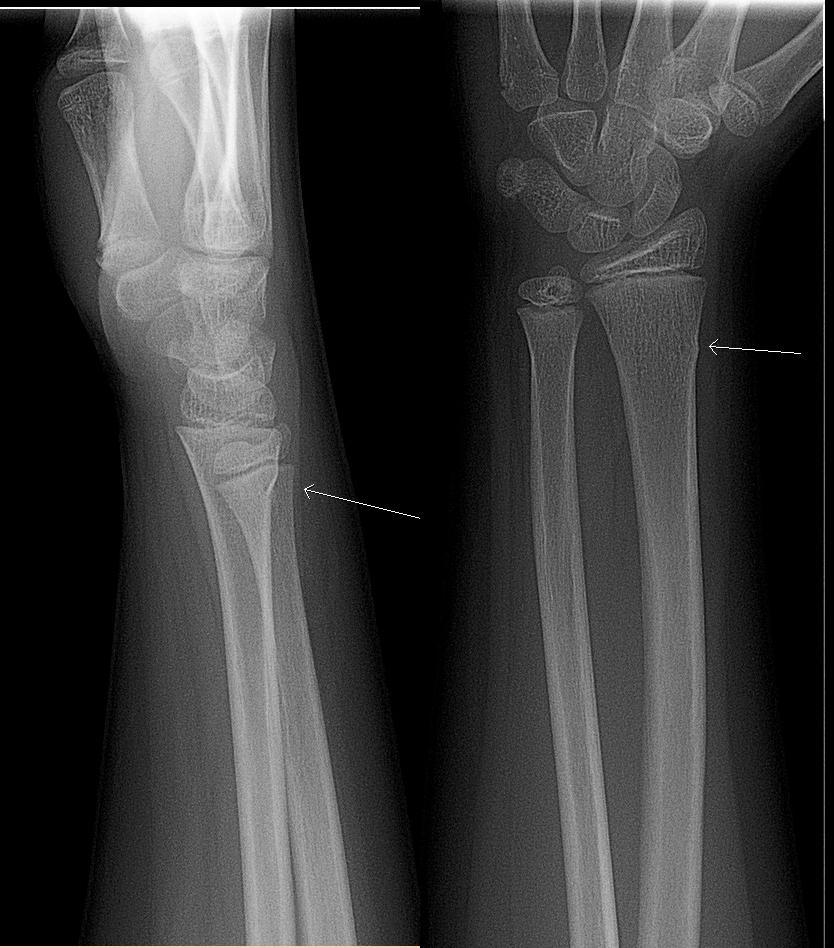

Oft bricht der Unterarmknochen eines Kindes nicht vollständig, sondern wird nur an der Oberfläche verformt. Dies nennt man eine "Greenstick"-Fraktur, die nicht operiert werden muss: Sie heilt mit einem Gipsverband. Diese Röntgenaufnahme zeigt eine Greenstick-Fraktur bei dem weißen Pfeil: nur eine kleine Ausbuchtung am Rand des Knochens und kein Bruch über die gesamte Länge:

Grünholzfraktur

Von Lucien Monfils (Eigenes Werk), CC BY-SA 3.0über Wikimedia Commons